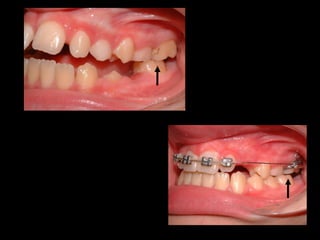

Normalmente, los primeros molares superiores erupcionan hacia vestibular y los inferiores hacia lingual, y después se enderezan.  Esto ocurre cuando hay lugar en el arco. Si no hay espacio, los molares mantienen esa posición y quedan las cúspides palatinas caídas.

Normalmente, los primerosmolares superiores erupcionan hacia vestibular y los inferiores hacia lingual, y después se enderezan. Esto ocurre cuando hay lugar en el arco. Si no hay espacio, los molares mantienen esa posición y quedan las cúspides palatinas caídas.